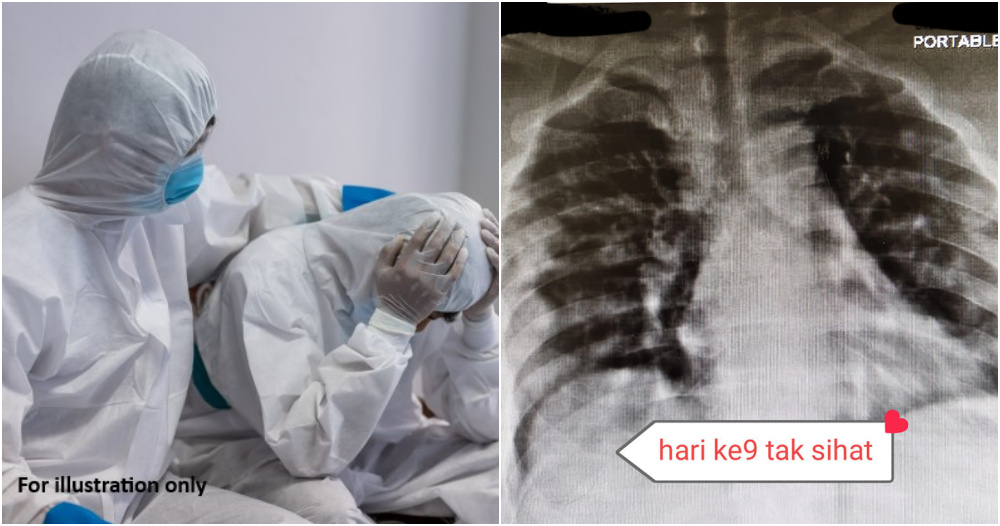

“This time after examination, the doctor heard an unpleasant sound in the lungs. They conducted a chest x-ray and the doctor saw a ‘Pneumonia’-like covid infection. Once again, they advised and persuaded the patient to do a swab test. Still, the patient rejected.

Due to the patient’s stubbornness to take the swab test, her health condition worsened upon entering the ninth day.

“Her breath seemed a little fast; she looked tired and breathless. The husband looked a little worried—oxygen in 94% -95% je. Conducted x-ray again. That’s it. Full-blown Covid-19 Pneumonia, it’s nothing else!”